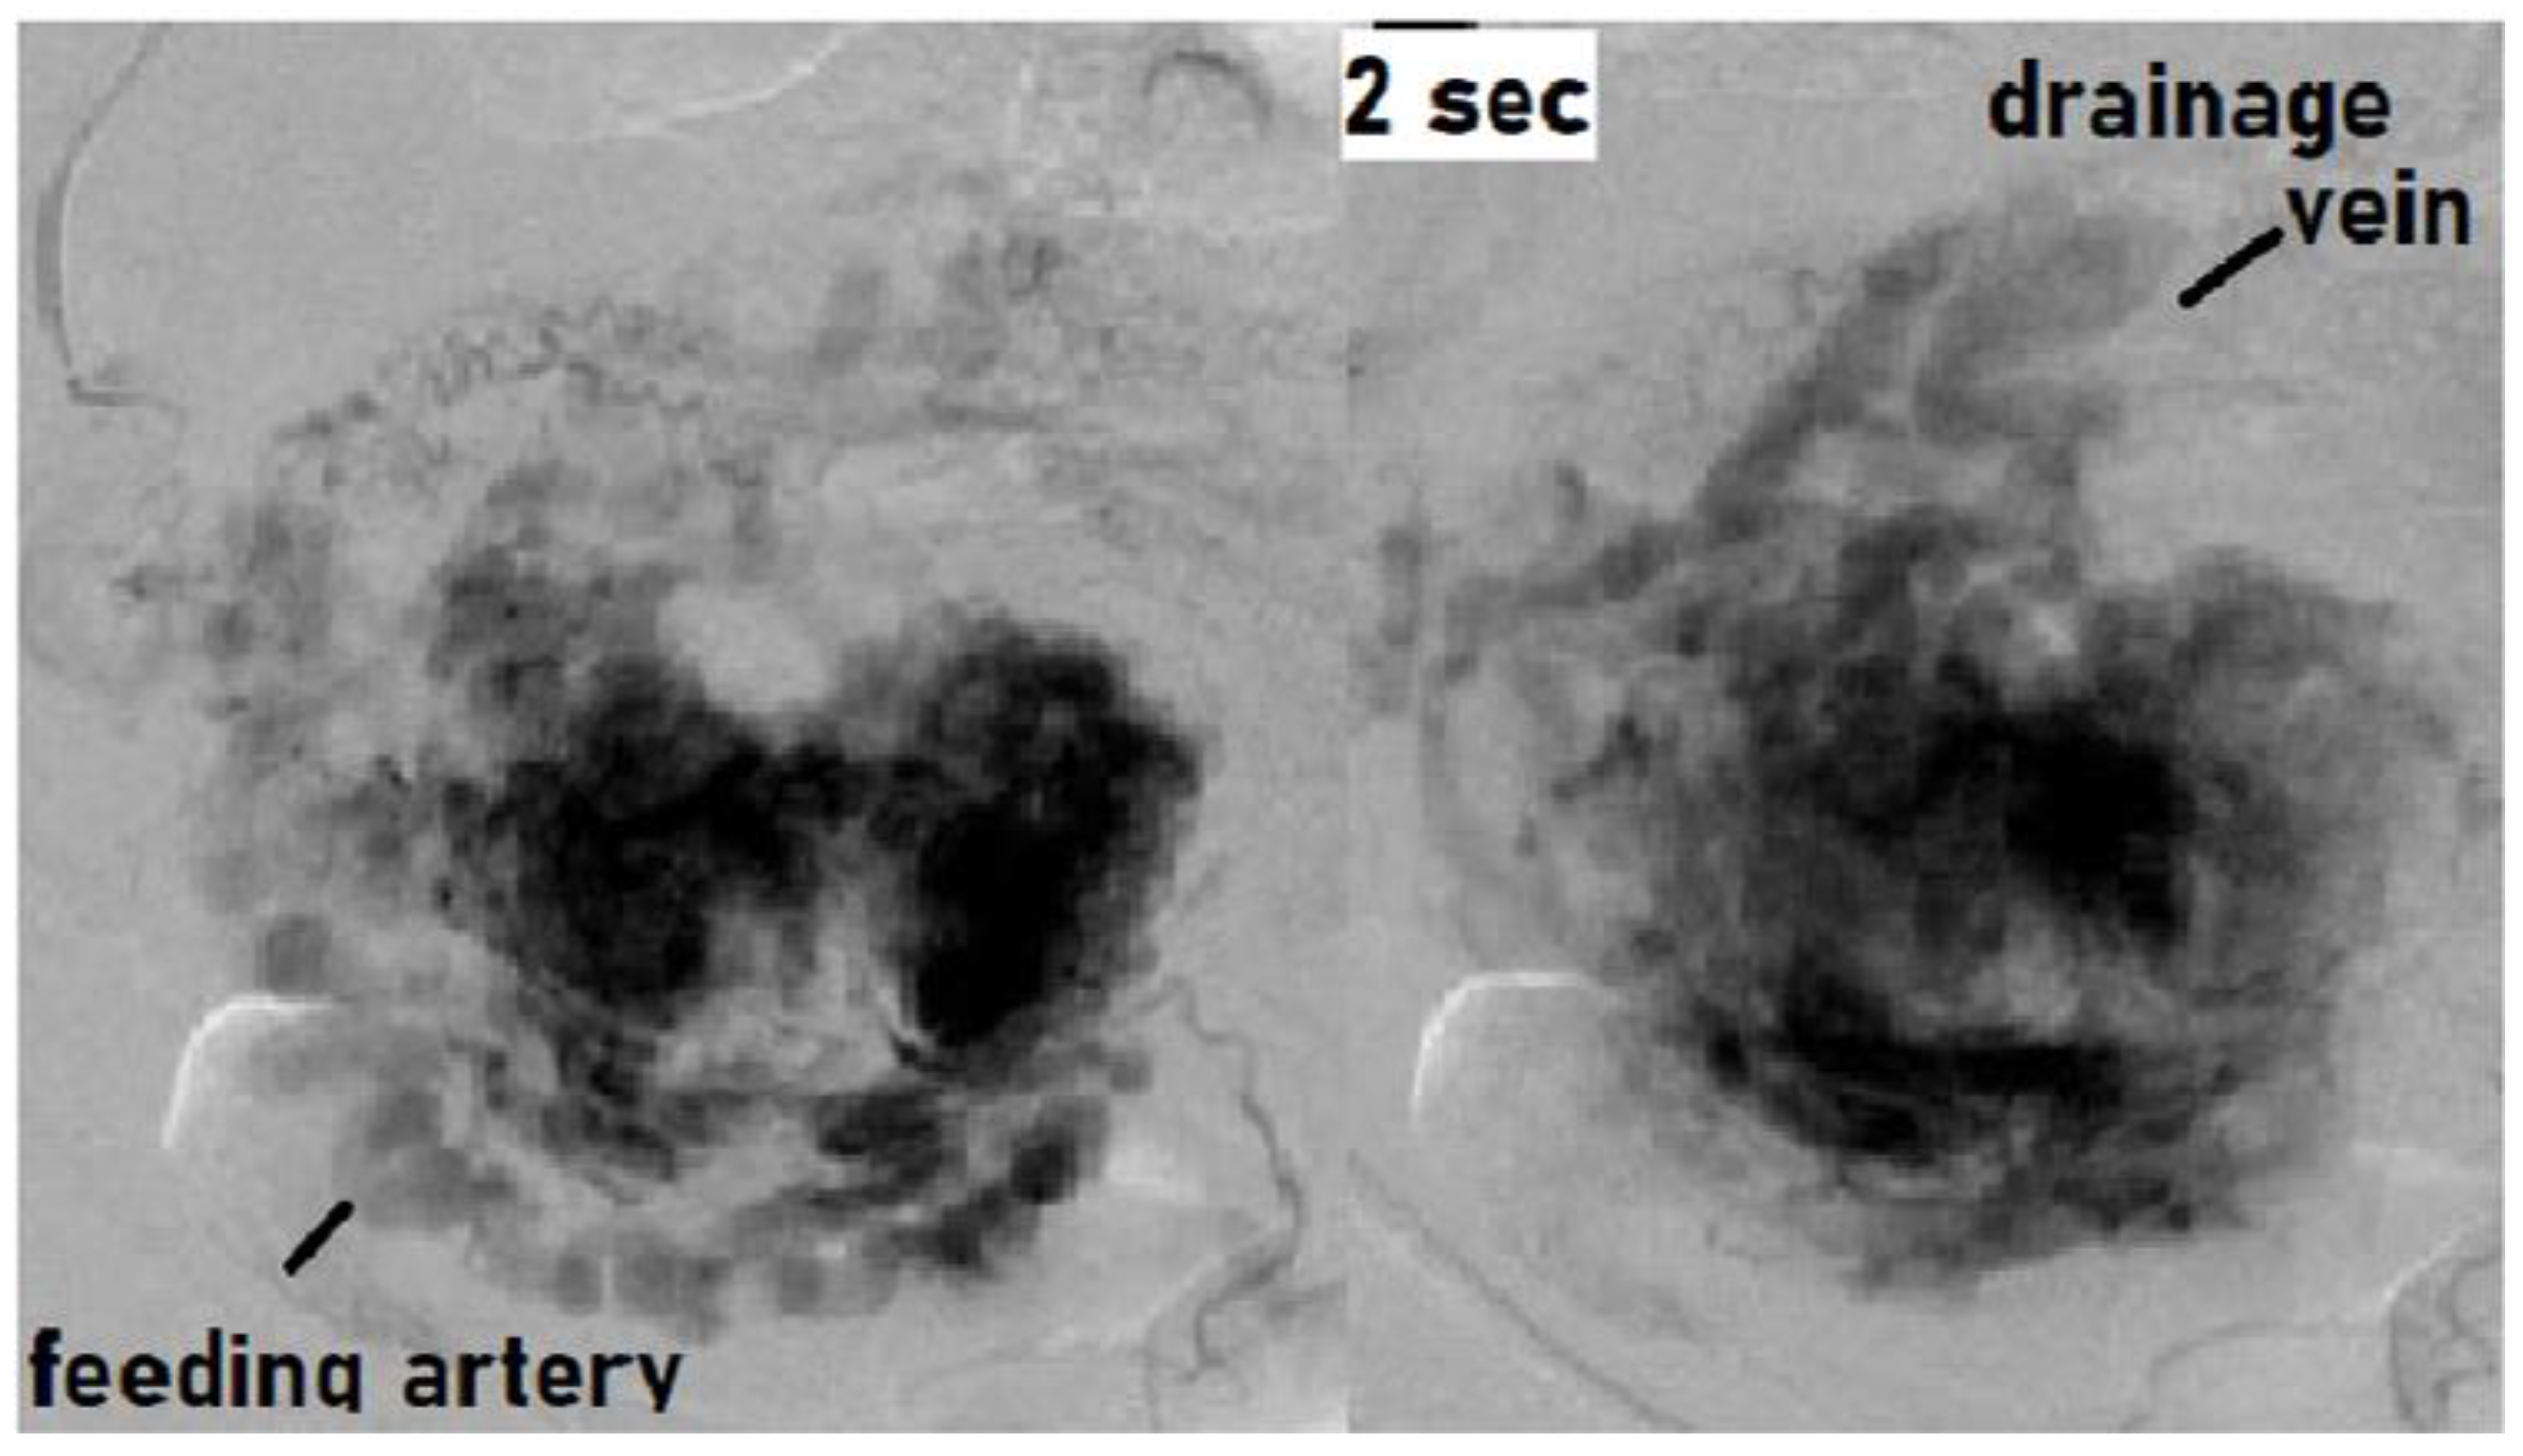

Angiography demonstrated abnormal engorgement in the arterial phase, with a thick venous phase visualized only 2 s later. This indicated the presence of an arteriovenous shunt, and an AVM with a hypervascular region was diagnosed (Figure 2) [20].

Findings of angiography: Abnormal engorgement in the arterial phase, with a thick venous phase visualized only 2 s later. This indicated the presence of an arteriovenous shunt. There was no pulsatile arterial perfusion in the remnant itself, where the contrast agent simply appeared to be leaking.

There was no pulsatile arterial perfusion in the remnant itself, where the contrast agent simply appeared to be leaking. The remnant was not the primary locus of the disease, but it was rather acting as a cover preventing major bleeding from the AVM. This case was correctly diagnosed as an AVM rather than RPOC with vascularization. UAE was performed, after which the remnant detached spontaneously, and the uterus was preserved.